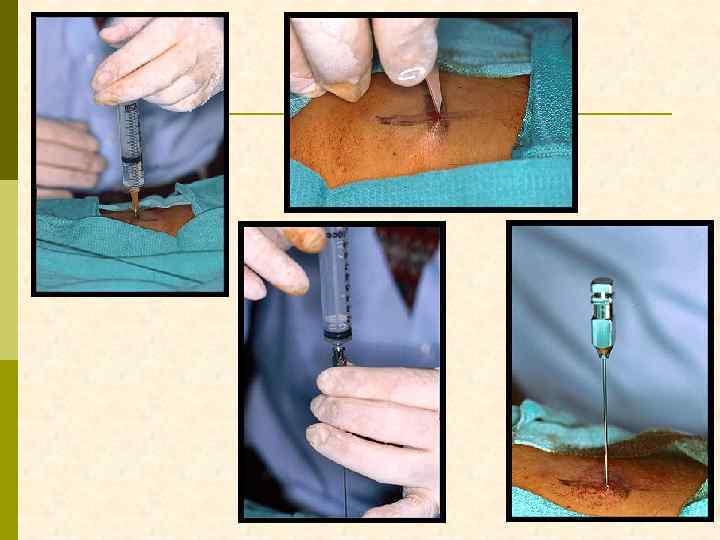

ВВЕДЕНИЕ «ПОИСКОВОЙ» ИГЛЫ

ВВЕДЕНИЕ БИОПСИОННОЙ ИГЛЫ В РЕТРОПЕРИТОНЕУМ